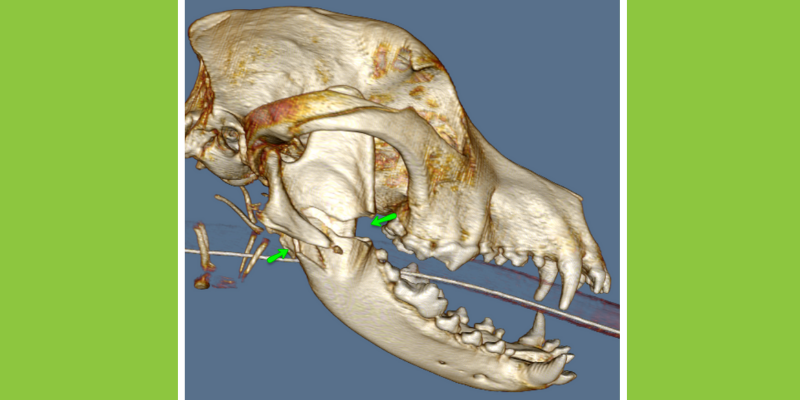

3D image reconstructed from a CT study of a dog hit by a car. The part of the mandible near the jaw (toward the left of the image) has a complex fracture. This CT study is essential in surgical planning of complex skull injuries such as this.